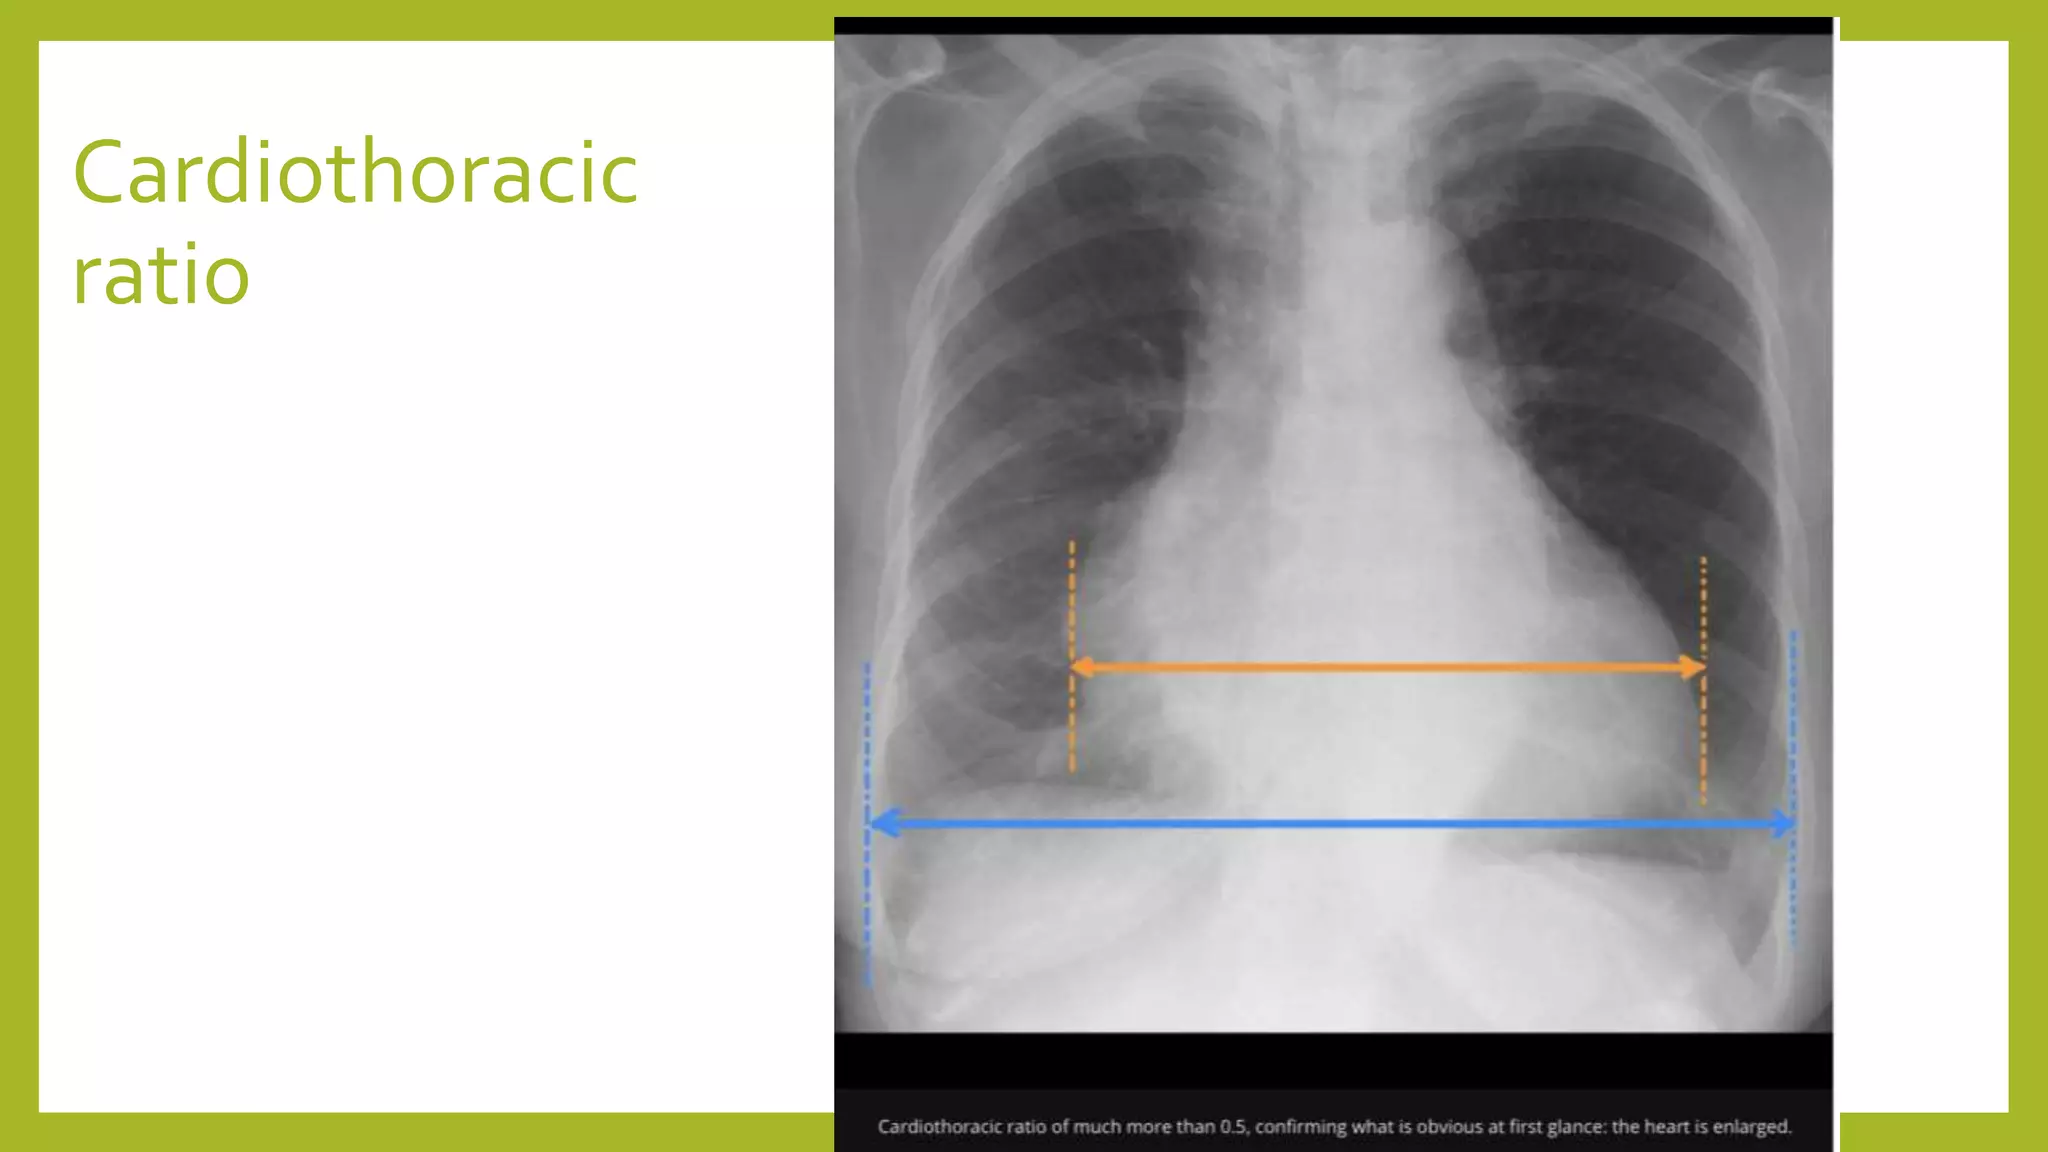

The document provides guidance on approaching and interpreting chest x-rays (CXR). It outlines steps to check the name, date and quality of the film, systematically scan the CXR looking for abnormalities, and determine if the lungs appear too white or black. Specific signs are described to help localize abnormalities, including the cardiac silhouette sign and pleural effusion signs. Examples are given of respiratory distress syndrome, tetralogy of fallot, transposition of great arteries, and total anomalous pulmonary venous return. The take home message is to summarize positive findings, compare to prior CXRs if available, and confirm findings with a radiologist.